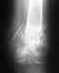

К вечеру заболела шея. Сильно проболела около недели, потом боль стала легкой и ноующей с периодическими усилениями. К травматологу так и не собрался, но в начале 2008 года все же решил обратиться. Сделали рентген и оказалось, что на одном из позвонков оторвалась связка с кусочком то ли кости, то ли хряща (не знаю, я ничего не понимаю в этом). Врач сказал, что от корсета из-за большого кол-ва времени, прошедшего с момента травмы, уже толку никакого. Выписал "Артрозан" и "Индометациновую мазь". Сказал, что заживать будет еще год, а потом ,мол, все будет ок. Но мне что-то не верится... Тем не менее, меня подобная неактивная позиция в лечении не устраивает (и так пол года просидел). Пока сидел, кстати, мазался мазью "Золотой ус" (как-то так называется... при травмах и т.д.). Подскажите, может быть я на свое выздоровлении как-то активнее могу повлиять?